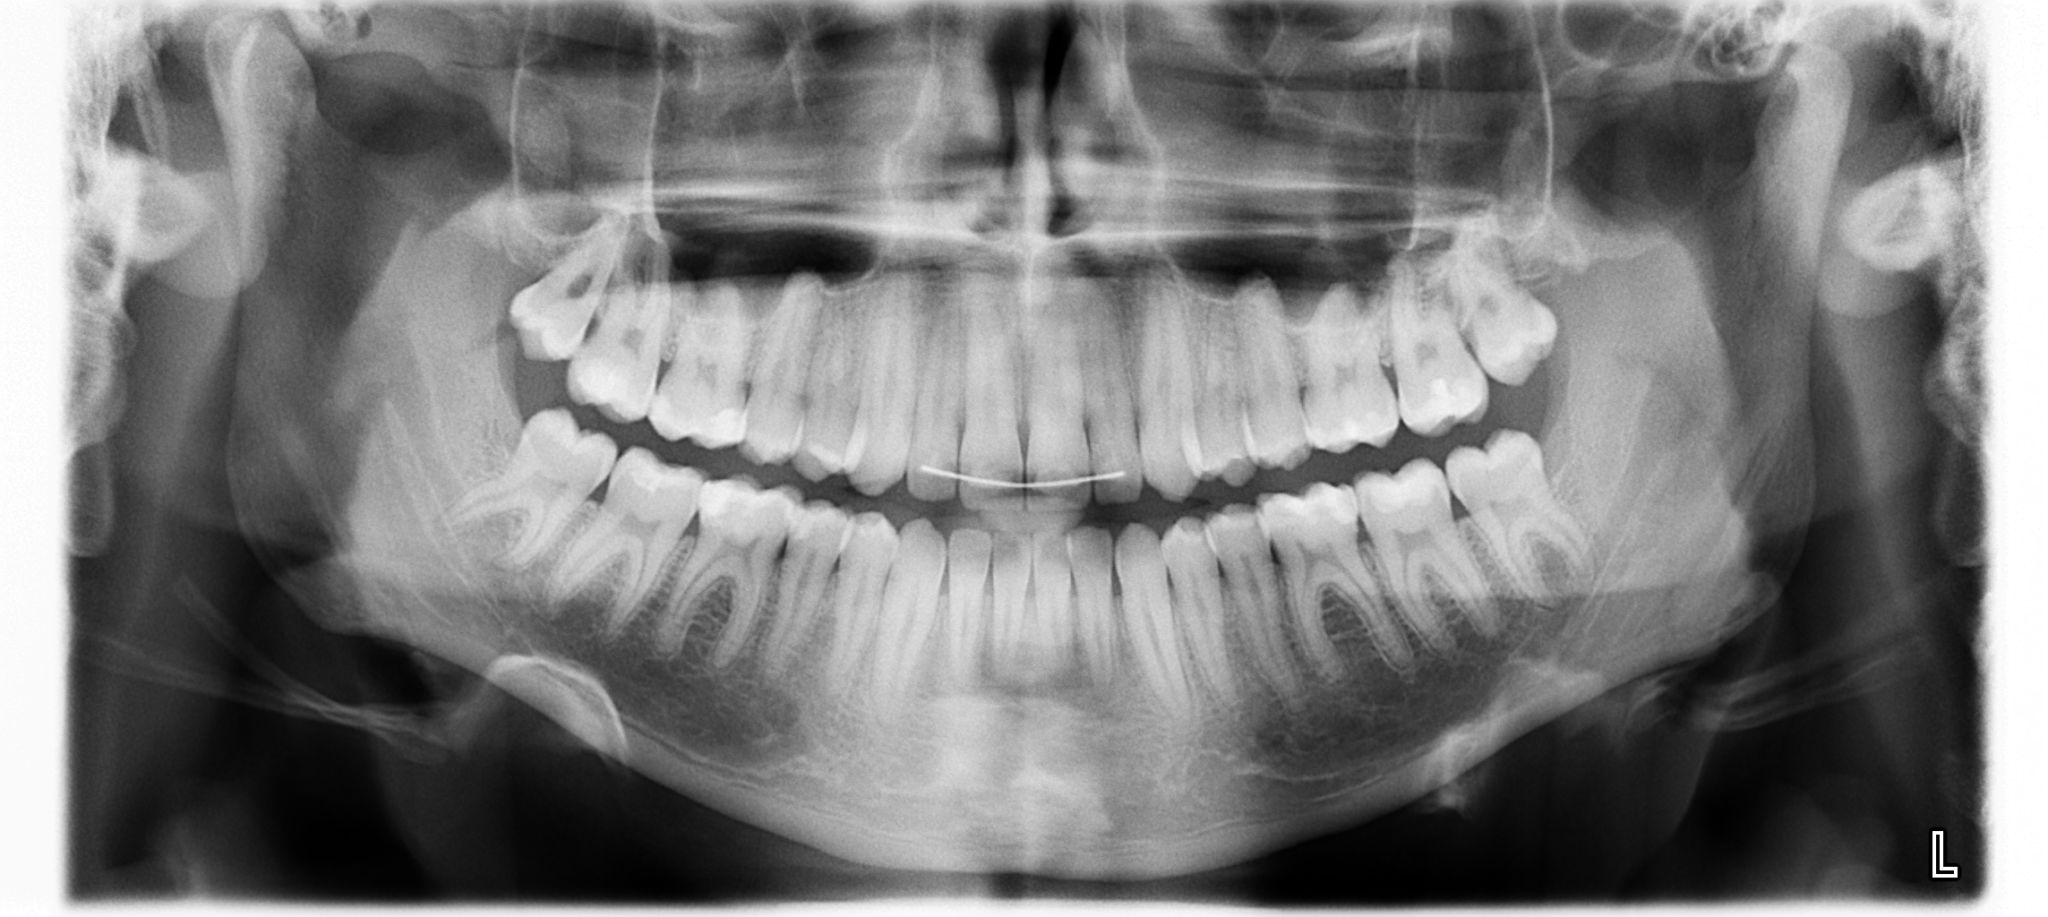

Ortopantomografia o ponoramica delle arcate dentali

La Radiografia Digitale è l’utilizzo della tecnologia digitale ci consente l’esecuzione dell’esame radiografico con una dose radiante estremamente ridotta, paragonabile a due ore di esposizione al sole. Lo studio si avvale inoltre di un moderno Ortopantomografo Digitale Tridimensionale per una diagnosi completa, accurata e precisa anche nelle situazioni più complesse.

In fase diagnostica e in alcuni casi anche intra e/o post-operatoria lo studio si avvale del utilizzo delle più innovative tecnologie radiografiche digitali, che nel pieno rispetto della salute del paziente permettono di ottenere immagini di elevata qualità in tempi praticamente immediati.

Tale sistema radiografico doigitale interfacciandosi con il sistema informatizzato dello stdio permetterà ingradimenti tridimensionali, misurazioni di spessori e quantità dei tessuti ai fini di garantire una progettazione accurata e ponderata della fase clinica.